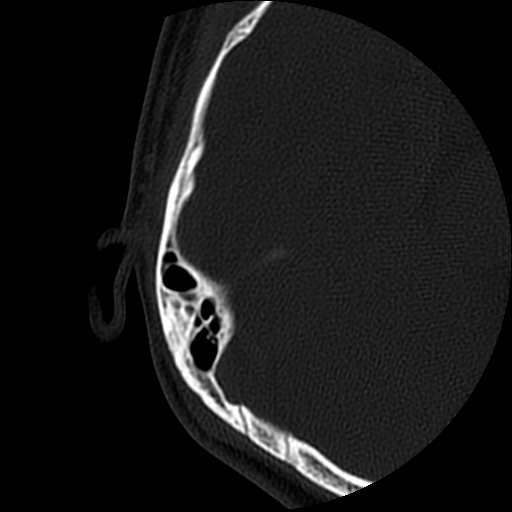

以下是引用随光逐影在2009-8-19 7:25:00的发言:[br]右侧慢性中耳乳突炎,右侧中耳腔及外耳道肉芽肿或胆脂瘤形成。